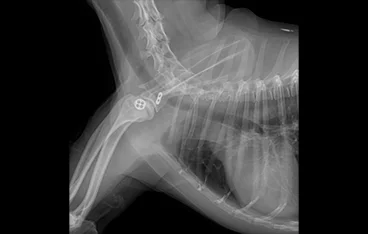

• 어깨탈구